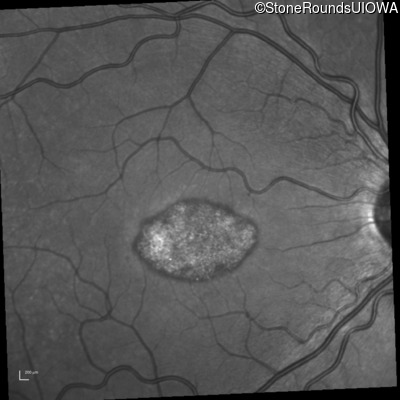

This 22 year old man had macular abnormalities noted incidentally at a routine eye exam at age 19. Since then, he has experienced a gradual loss of acuity particularly in the left eye.